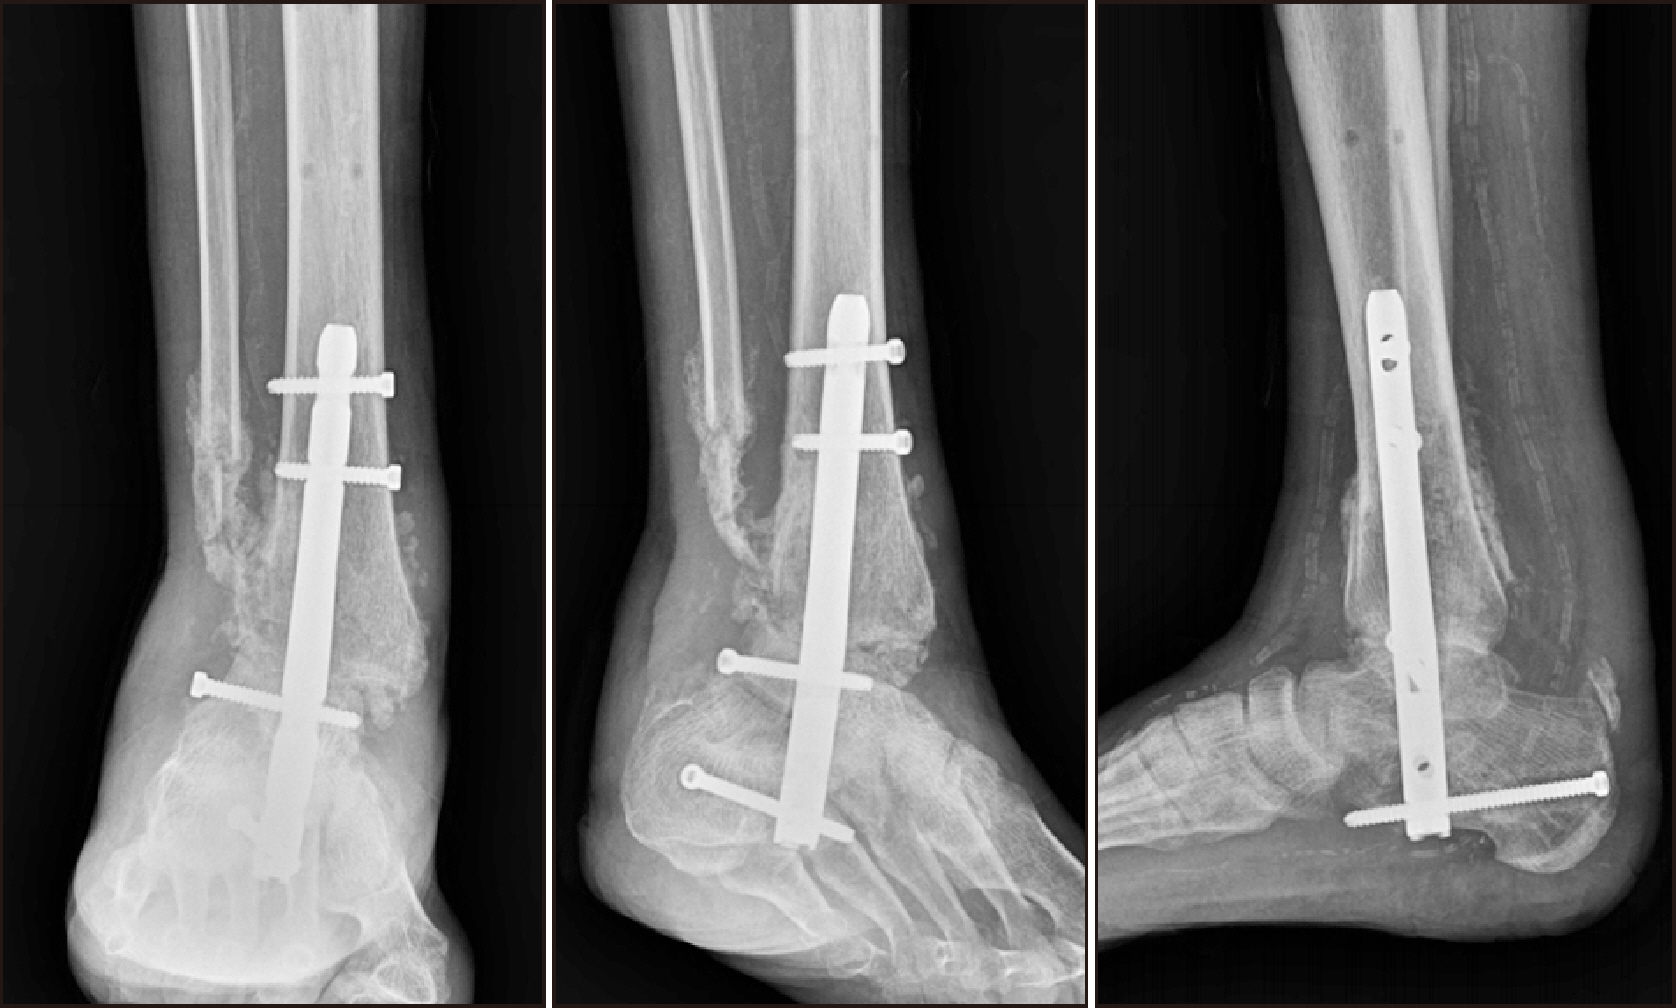

Charcot neuroarthropathy (CN), also known as Charcot arthropathy, is a complex, progressive disorder primarily affecting the foot and ankle. This case report describes a multifaceted management strategy for a 54-year-old male with diabetes mellitus, end-stage renal disease, and presumed underlying Charcot arthropathy who experienced a traumatic ankle fracture. The initial surgical plans were delayed because of systemic infection indicators, including elevated C-reactive protein levels and high fever. The patient underwent multiple surgical interventions and faced challenges, including metal failure, implant-associated infection, and tibiotalar joint dislocation. A multidisciplinary approach involving orthopedic surgeons, nephrologists, and endocrinologists was crucial for managing the case effectively. In particular, the patient declined a below-knee amputation and opted for comprehensive surgical intervention, resulting in improved functionality at the latest follow-up. This case highlights the complexities of managing CN in patients with multiple comorbidities and emphasizes the need for a nuanced, patient-centered approach.